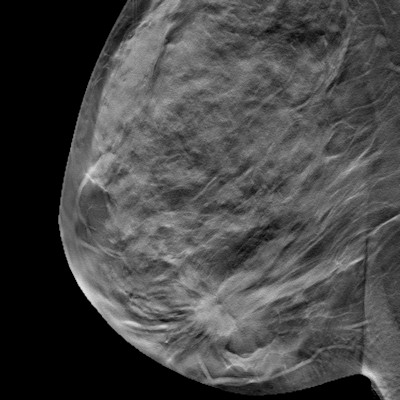

Surveillance could be a preferred management strategy for lobular neoplasia detected on digital breast tomosynthesis (DBT), according to research published August 29 in Clinical Imaging.

A team led by Yukun Gao, MD, and Manisha Bahl, MD, from Massachusetts General Hospital in Boston found a low upgrade rate of screening DBT-detected lobular neoplasia, meaning surgery could be avoided for women with atypical lobular hyperplasia and in women with screening-detected calcifications leading to diagnosis.

Lobular neoplasia refers to atypical lobular hyperplasia and lobular carcinoma in situ (LCIS), high-risk lesions that indicate an increased lifetime risk of breast cancer. Previous 2D mammography studies suggest wide variability in upgrade rates of lobular neoplasia, ranging from 0% to 45%. This has led to inconsistent management, the researchers noted.

Little data exists on such upgrade rates for lobular neoplasia detected on DBT, according to Gao and Bahl. They sought to add to the literature through an investigation of upgrade rates on DBT-detected cases, as well as determine the imaging and clinicopathological features linked to higher upgrade risk.

The team included data collected between 2013 and 2020 for 107 women with an average age of 55 years. The women had a total of 110 cases of atypical lobular hyperplasia and/or LCIS and either underwent surgery (n = 89) or at least two-year imaging surveillance (n = 21).